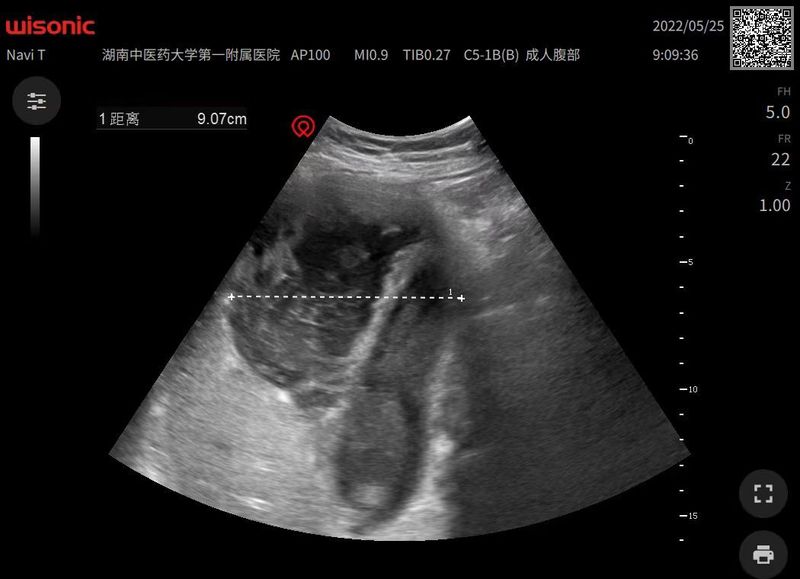

超聲引導(dǎo)下經(jīng)皮肝膽管引流術(shù)(PTCD),梗阻性黃疸退黃效果不錯,圖1-3左肝PTCD,圖2-6左右肝管雙側(cè)PTCD。圖8-9超聲引導(dǎo)下肝腫塊活檢術(shù)。PTCD外引流聯(lián)合ERCP內(nèi)引流已成為我科特色。目前我科開展超聲引導(dǎo)下肝膽胰腫塊活檢術(shù);肝膿腫,腹腔膿腫穿刺引流術(shù);肝囊腫硬化治療術(shù),超聲引導(dǎo)下肝腫瘤微波消融術(shù)。

這是一例膽囊結(jié)石膽囊炎并發(fā)肝膿腫的患者。患者既往有膽囊結(jié)石伴膽囊炎病史,又因為腎病綜合征長期服用激素,機體抵抗力下降,十多天前膽囊結(jié)石膽囊炎發(fā)作,又因為家庭變故耽誤了治療,患者因腹痛,嚴(yán)重感染來院,檢查發(fā)現(xiàn)膽囊結(jié)石膽囊炎合并肝膿腫,病情危重,超聲引導(dǎo)下穿刺抽出膿液約500毫升,感染指標(biāo)明顯好轉(zhuǎn),避免了膿毒血癥,感染者休克嚴(yán)重情況的發(fā)生